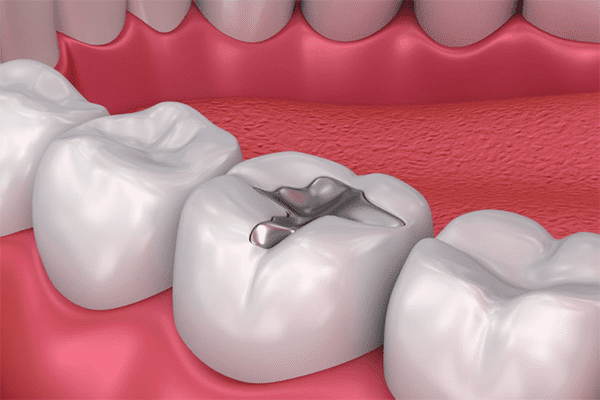

Dental Clinic in Narasimhanaickenpalayam

At GuGu Dental Clinics, we take delight in being one of the most trusted dental clinics in Narasimhanaickenpalayam, supplying whole oral care for the complete own family. From routine checkups to advanced dental treatments, our team of professional dentists ensures that every patient gets personalized and extremely good care.